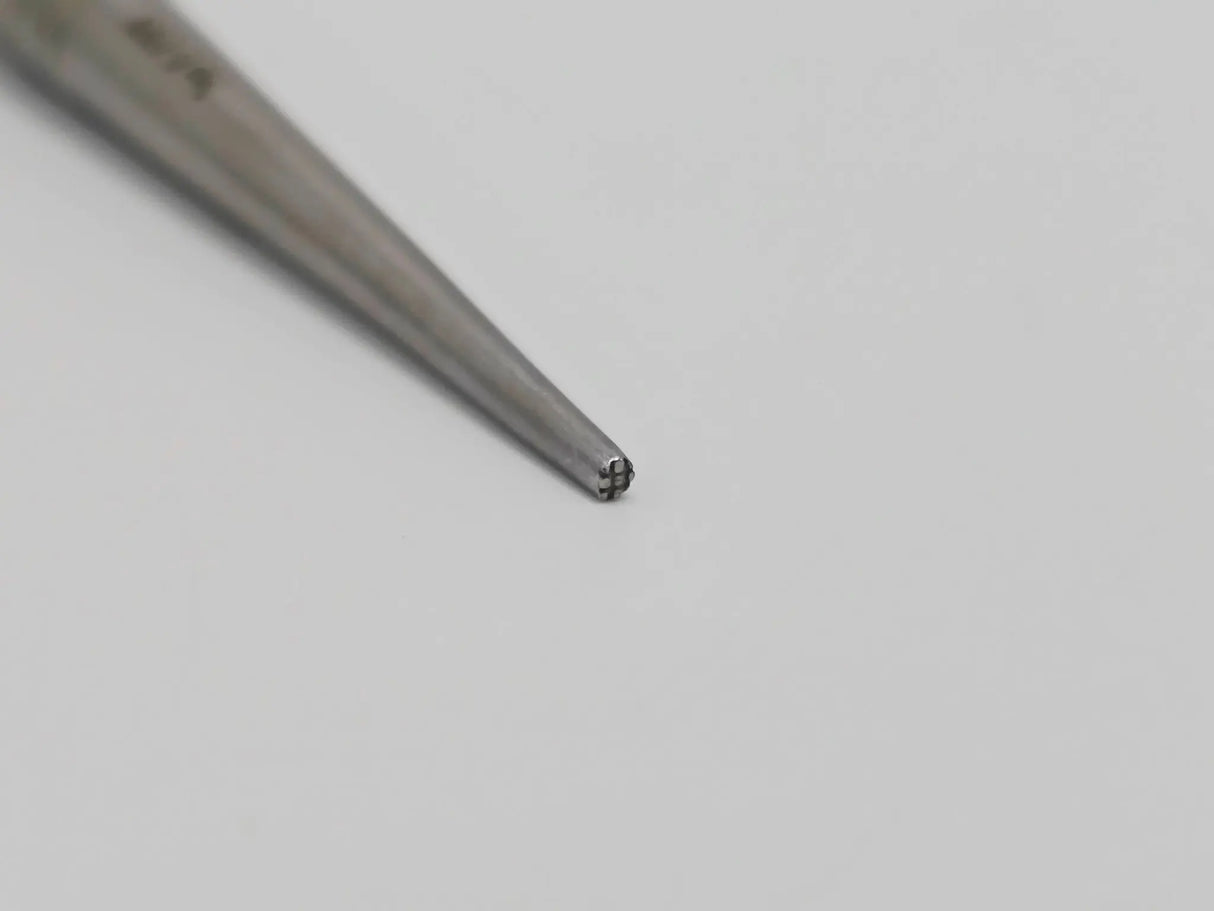

The V. Mueller OS1610-002 is a bone tamp with a 2 mm cross-serrated tip, measuring approximately 6¼ inches in overall length. The serrated tip is designed to grip and compact bone material during orthopedic procedures, aiding in precise manipulation and stabilization. The model number “OS1610-002” is engraved for positive identification.

Crafted from surgical-grade stainless steel, this tamp offers durability and resistance to corrosion under repeated use and sterilization. Its shaft is straight and rigid, providing controlled force transmission, while the serrated end maintains grip even in slippery or irregular bone surfaces.